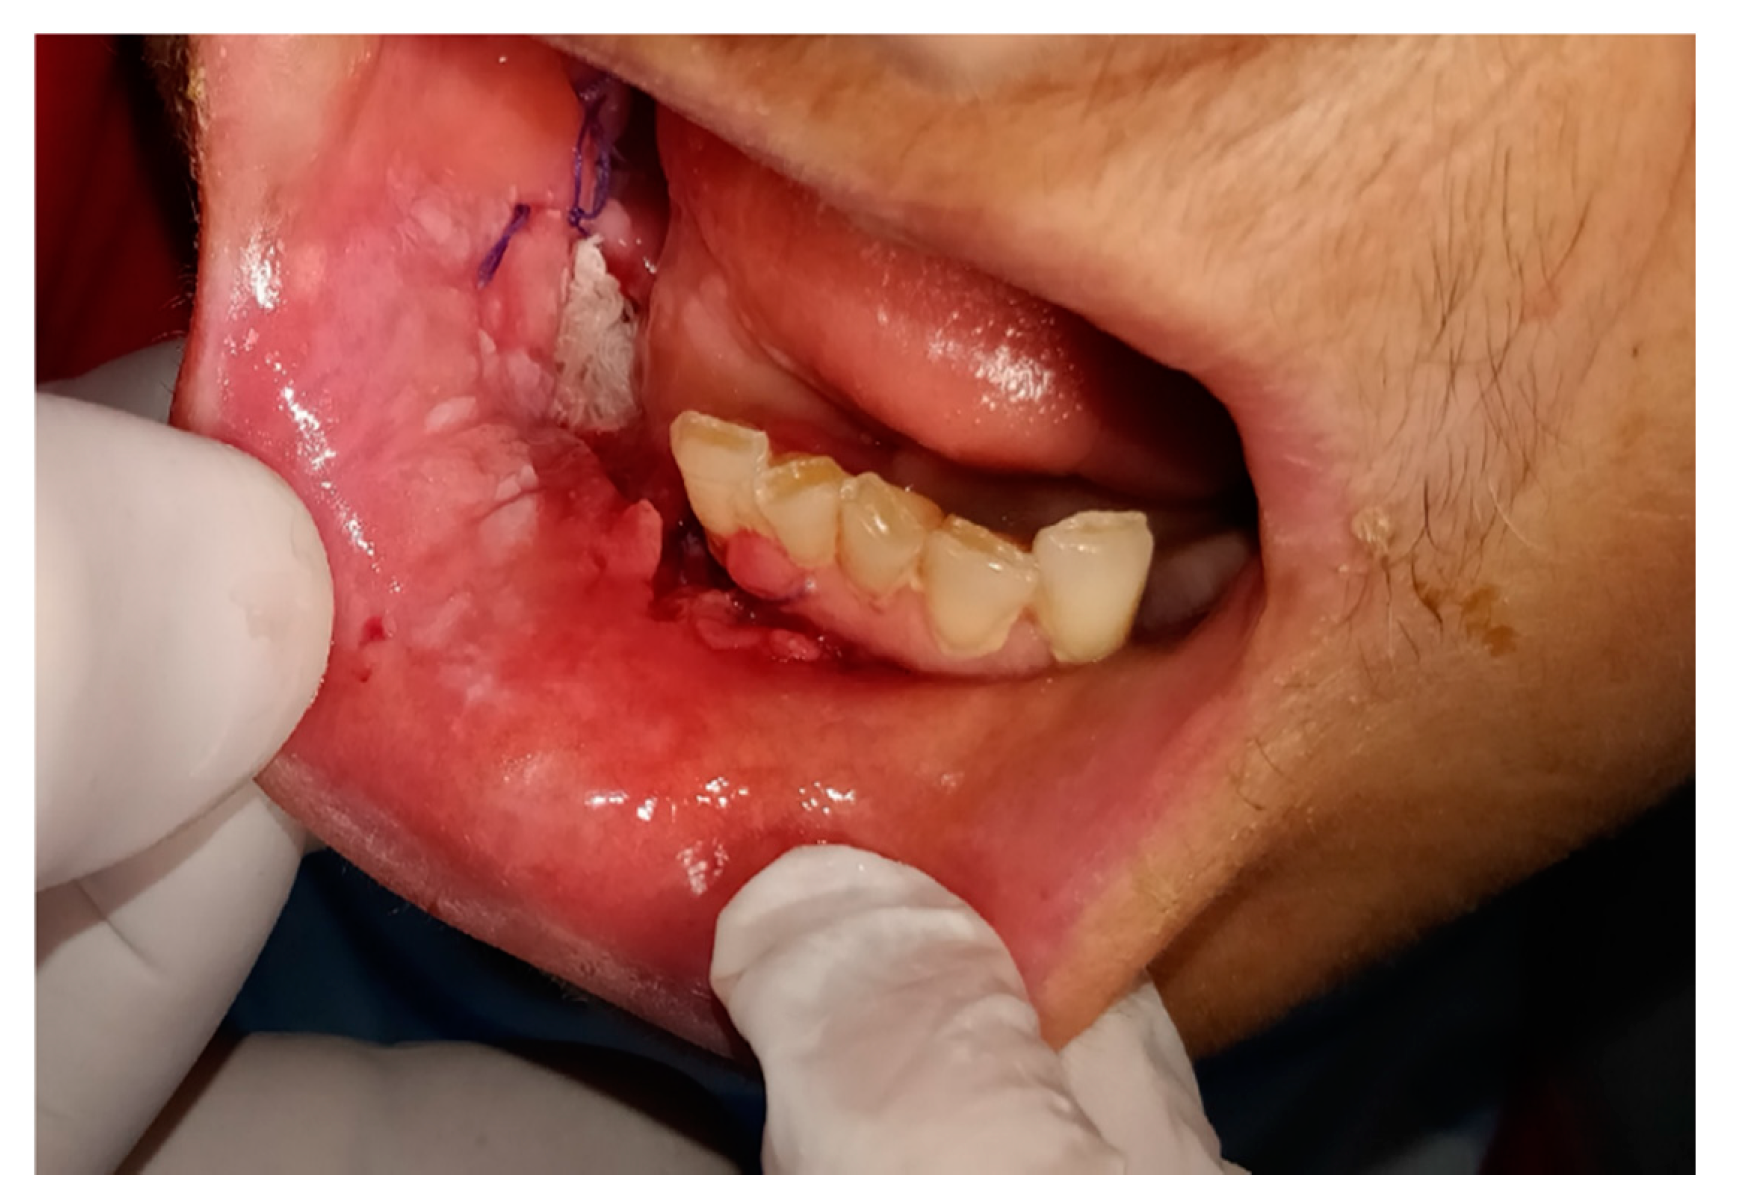

| SubGroup B1 Neoplasm 1st visit | 12 contacts | Skin Carcinoma: 3 | Skin Biopsy: 2 |

| Mucosa Oral Carcinoma: 8 | Oral Biopsy: 4 | ||

| Submandibular gland Carcinoma: 1 | |||